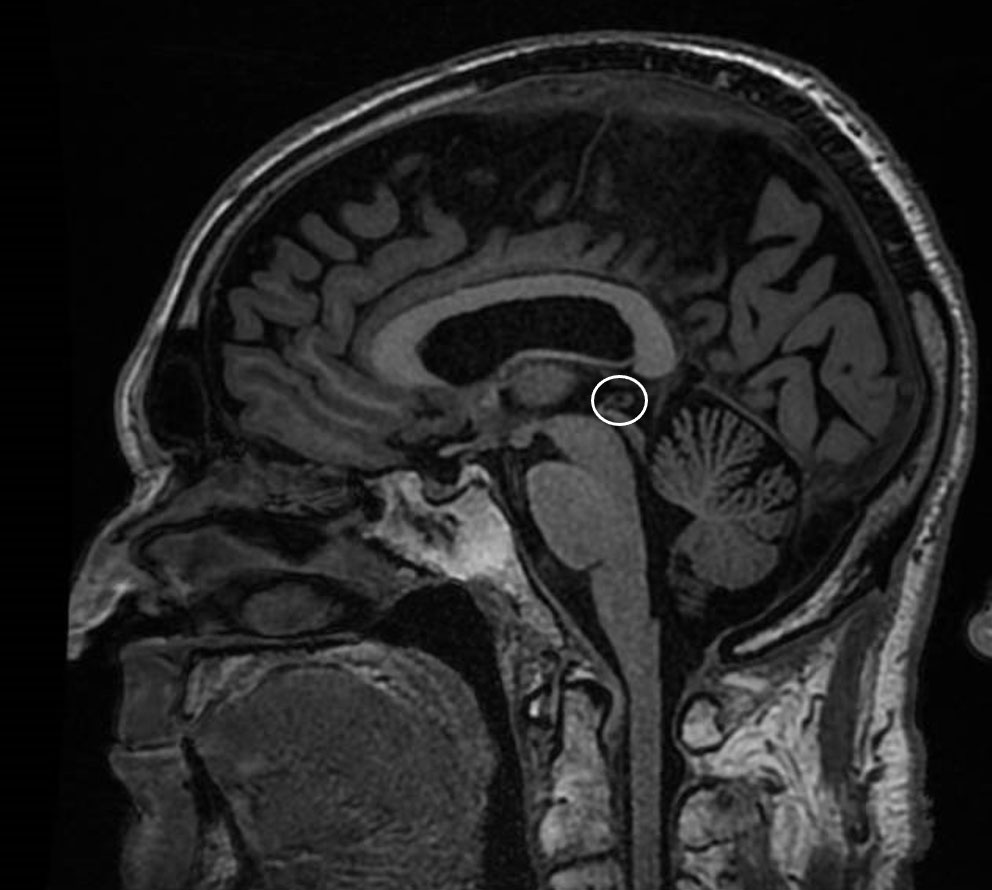

Además, en algunas ocasiones, el trastorno del sueño es la primera manifestación de una enfermedad más compleja, por ejemplo, de una enfermedad de Parkinson, por lo que su correcta identificación nos permite anticiparnos al diagnóstico de la enfermedad subyacente, cuyos síntomas más conocidos pueden aparecer años después.